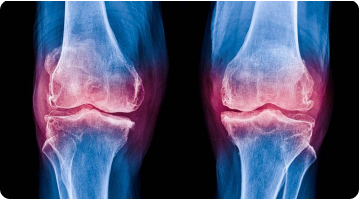

Knee pain can greatly affect one’s mobility and day-to-day life. For those with severe joint damage, knee replacement surgery may be recommended. The two main options are total knee replacement (TKR) and partial knee replacement (PKR). Here, we describe the two and explain which might be more suitable for your circumstances.

Knee pain is a common problem affecting people of all ages, from athletes pushing their limits to seniors managing everyday tasks. Let us discuss more about knee...